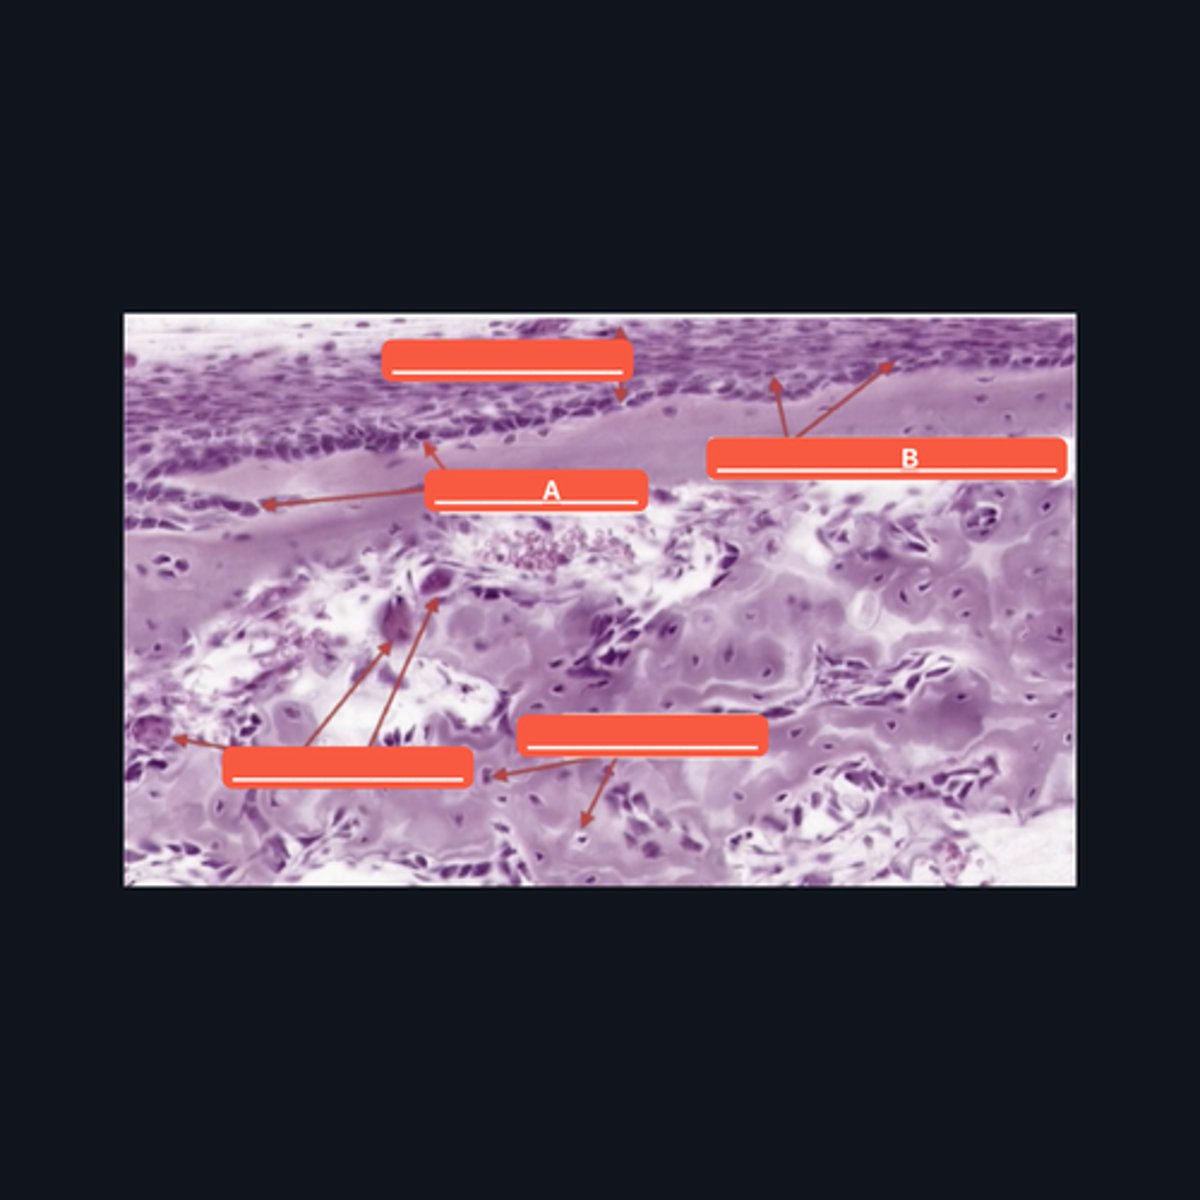

Fibrocartilage; intervertebral disc, articular disc, glenoid and acetabular labra

What type of cartilage is in the image? Where is this specific type of cartilage found?

Collagen fibers

This type of cartilage is abundant in what fibers?

Dense regular connective tissue; chondrocytes; lacunae

This cartilage is commonly mistaken as _____. However, when examined closely, _____are contained in _____ (identify pointed structures), making it a cartilage.